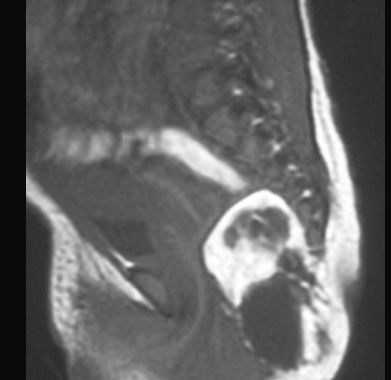

POTWORNIAK

MR